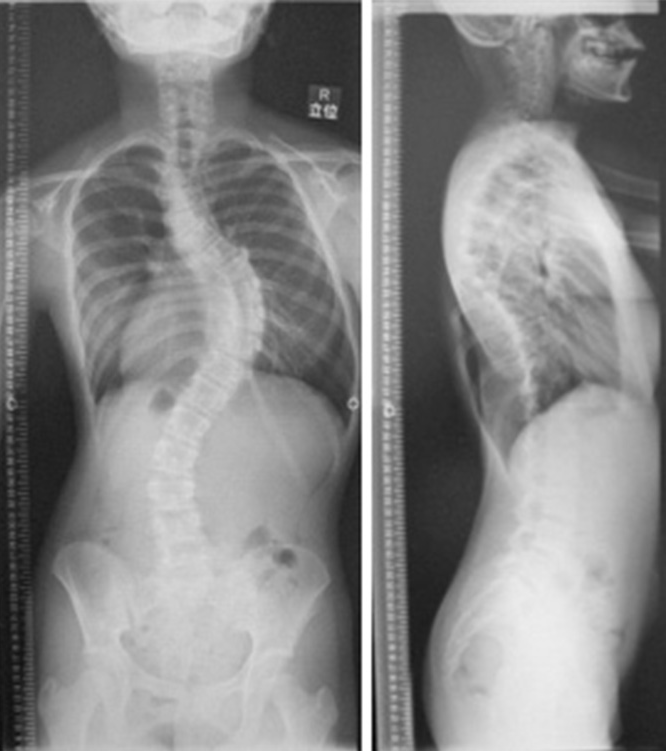

脊柱畸形,包括脊柱側(cè)彎達青春期,較近一直在成人脊柱畸形的病例,其中包括側(cè)成人脊柱側(cè)凸脊柱側(cè)彎后增加,。對于特發(fā)性脊柱,專門的醫(yī)療檢查,治療已經(jīng)協(xié)商前提是需要脊柱側(cè)彎門診疾病。對于治療,初次隨訪,做保守治療,包括支柱治療。然后,每個骨成熟度的患者,脊柱側(cè)彎的程度手術(shù)治療將被選中。關(guān)于成人脊柱畸形患者,充分揉計劃和你的家人,我們的手術(shù)。冠狀面,以及在矢狀面上的平衡為重點,各類截骨術(shù),必要的組合,你可能要選擇較多骶骨骨盆的融合。近年來手術(shù)將有增加的趨勢,但什么手術(shù)不受威脅比我們認(rèn)為前列。術(shù)中,采用神經(jīng)刺激器(SEP,MEP等),我們將繼續(xù)進行手術(shù),同時檢查是否不受威脅進行手術(shù)操作。